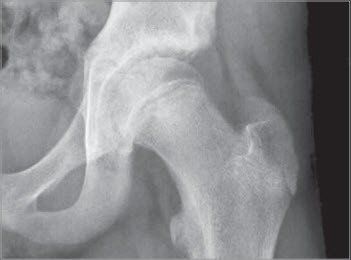

chronischer Epiphysiolysis capitis femoris

2 AP-Projektion der linken Hüfte mit chronischer Epiphysiolysis capitis femoris. Die Epiphysenfuge zeigt sich unregelmässig verbreitert und die Epiphysenhöhe vermindert